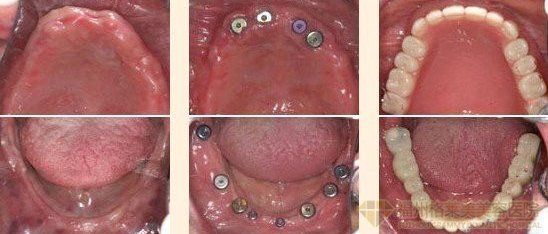

广州越秀圣贝口腔门诊部口腔采用的普士即刻种植牙是目前连锁对口腔牙列缺损、牙列缺失修复的较佳。普士即刻种植是通过术前对患者牙槽骨进行数字化的影像扫描定位,并根据相关数据制作定位导向,而后"人工牙根"顺着定位导向植入牙槽骨,当"人工牙根"与牙槽骨生物相容稳固后即可进行镶牙,种植牙被誉为人类的"第三副牙齿"。